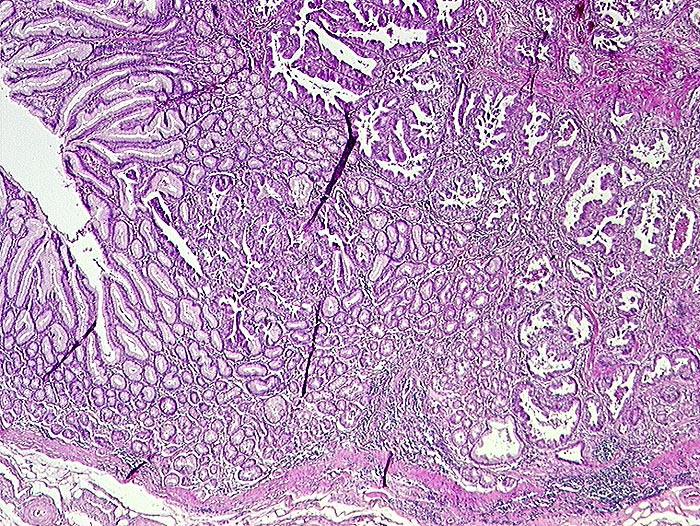

PathoPic ID 1342 - Adenokarzinom intestinaler Typ nach Lauren

Adenokarzinom intestinaler Typ nach Lauren

maligner Tumor

Magenantrum

Oesophagus, Magen

Magenantrumschleimhaut links. Rechts davon unregelmässig geformte Tumordrüsen.

Histologie